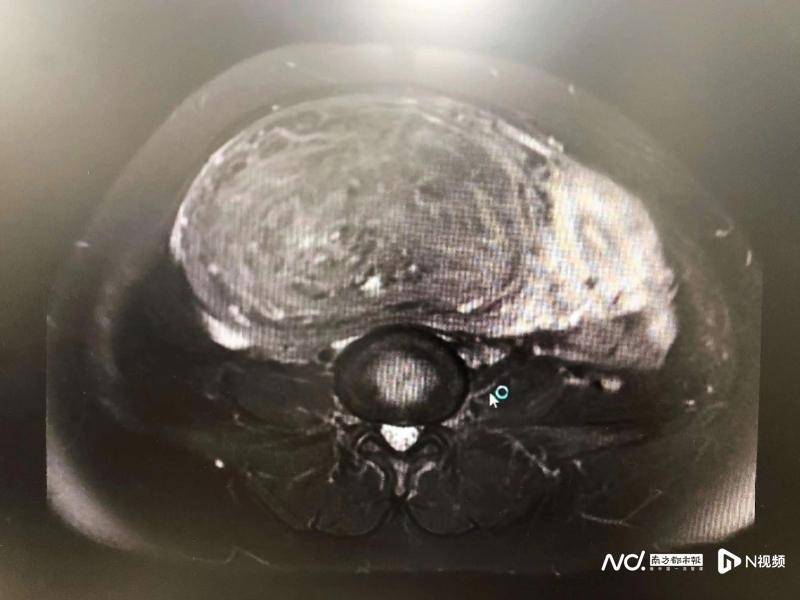

据悉,该名患者9年前就患有子宫肌瘤,2019年在坪山区人民医院超声检查时提示肌瘤已经有足月胎儿头那么大了,医生建议住院手术治疗,但是患者由于多种原因未住院。近日,在医院开展的免费两癌筛查项目中,患者再次复查,但检查结果不禁让医生也吓了一跳:患者子宫肌瘤长得飞快,肚子已经大到如怀孕足月一般,且生长速度惊人,必须尽快安排手术。

子宫肌瘤,是育龄期及围绝经期女性最多见及常见的肿瘤,但是如此巨大、位置特殊的子宫肌瘤实属罕见。为防止病情恶化,妇科李晓燕主任医师立即为患者安排了住院,与团队成员认真研究患者的诊疗方案,包括充分的术前检查、术后护理等,为患者制定了详细周密的手术方案。因肌瘤过大,而且为特殊部位的阔韧带肌瘤,考虑患者年龄50岁了,医生决定采用经腹子宫全子宫切除术,双侧输卵管切除术。

一切准备就绪,4月15日上午,手术顺利实施。术中主刀医生李晓燕发现患者子宫解剖结构严重变形,盆腔中巨大肿瘤来源于子宫右侧阔韧带,临床上十分罕见,没有固定的手术模式可供参考,而且肿瘤巨大,致使包块及周围组织结构边界不清,并且由于肿瘤表面的营养血管粗大密集、盘根错接,加大了手术的难度和出血的风险。在多学科通力协作下,医护人员凭借丰富的临床经验和精湛的操作技术,历经2个多小时,顺利为患者摘除了5公斤重的肌瘤,且术中失血仅400ml,手术十分成功。患者安全返回病房。